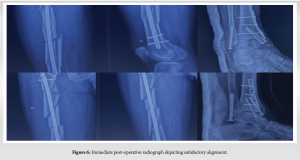

It was decided to use an intramedullary nail for closed reduction and internal fixation (CRIF) of the triple-segmental shaft femur fracture. Fixation of the bimalleolar fracture was done with antiglide plating and cannulated cancellous screws. The other fractures were managed conservatively.

The patient had an uneventful post-operative course. An immediate post-operative radiograph depicted satisfactory alignment (Fig. 6). He was advised of early mobilisation with weight-bearing limitations . Radiographs 3 months after surgery showed signs of fracture healing and satisfactory alignment (Fig. 7). The patient continued physiotherapy to regain range of motion and strength in the injured limb. Radiographic evaluation 1 year after surgery confirmed complete fracture union (Fig. 8). The other fractures–the patella, acetabulum, cuboid, and bimalleolar–had also appropriately healed. The patient returned to his pre-injury activity level without limitations and reported no persistent pain.